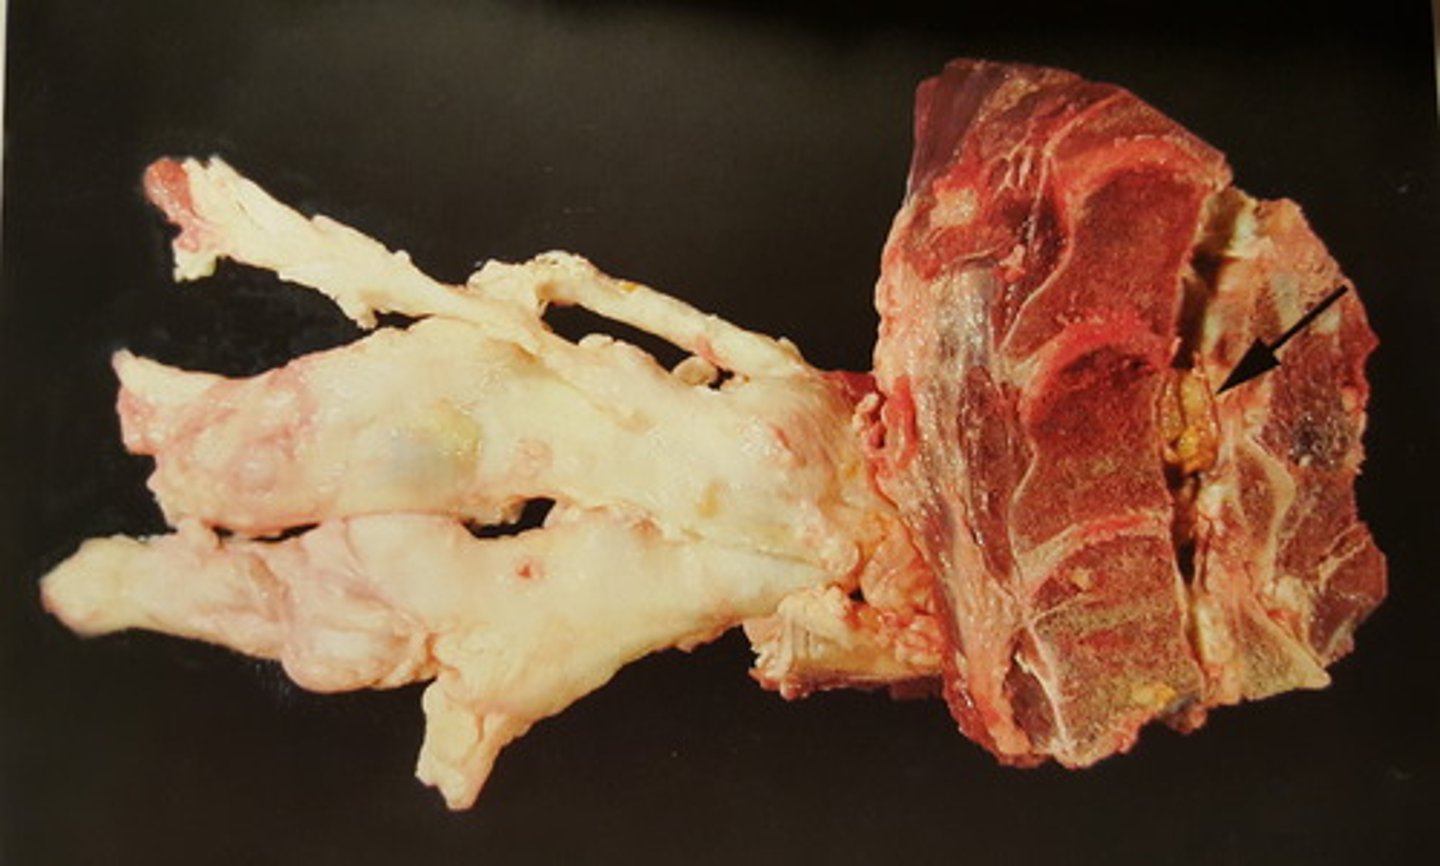

udbredt forekomst af Schwannomer

Perifere nervesystem hos okse. Patoanatomisk diagnose?

multiple Schwannomer

Intercostalnerver hos okse. Patoanatomisk diagnose?

R=ribben, N=nerver, I=muskulatur